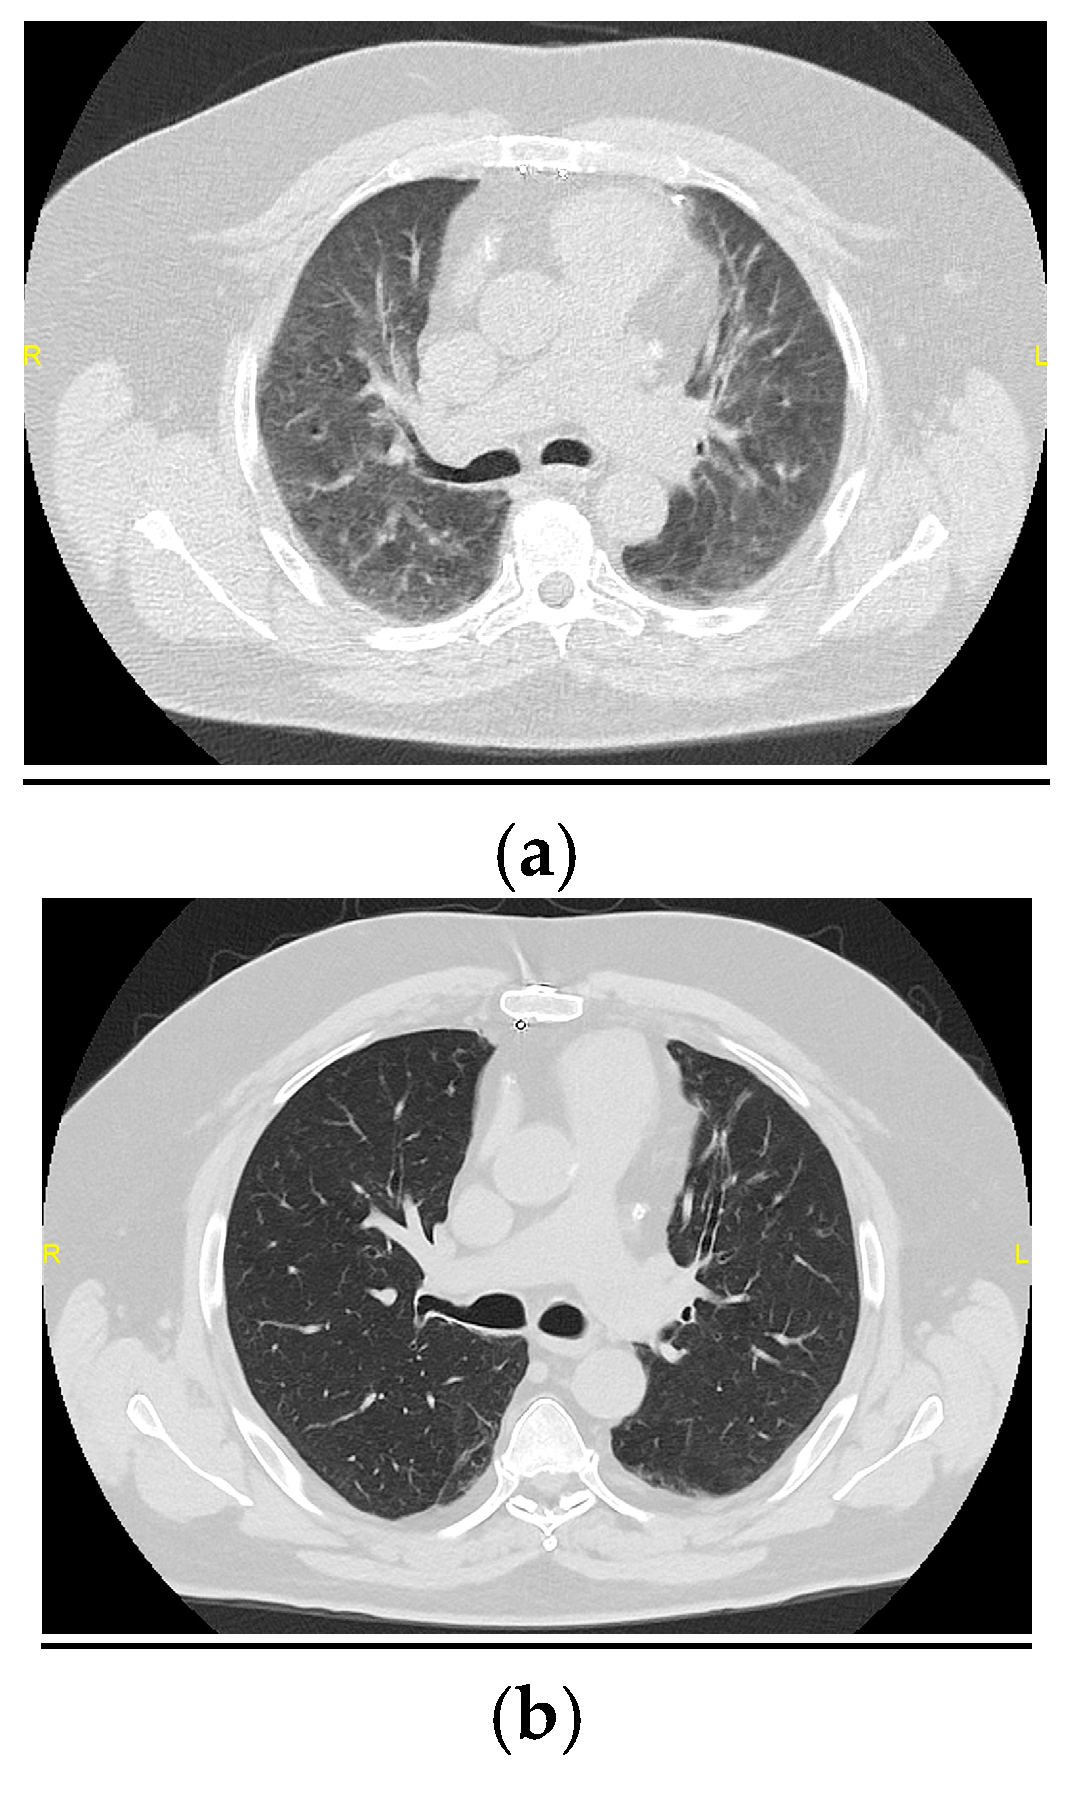

3.2. Changes in the Main Radiological Patterns and Findings from 6 to 12 Months After Hospital Discharge

3.2.1. Radiological Patterns

3.2.2. Main Radiological Findings